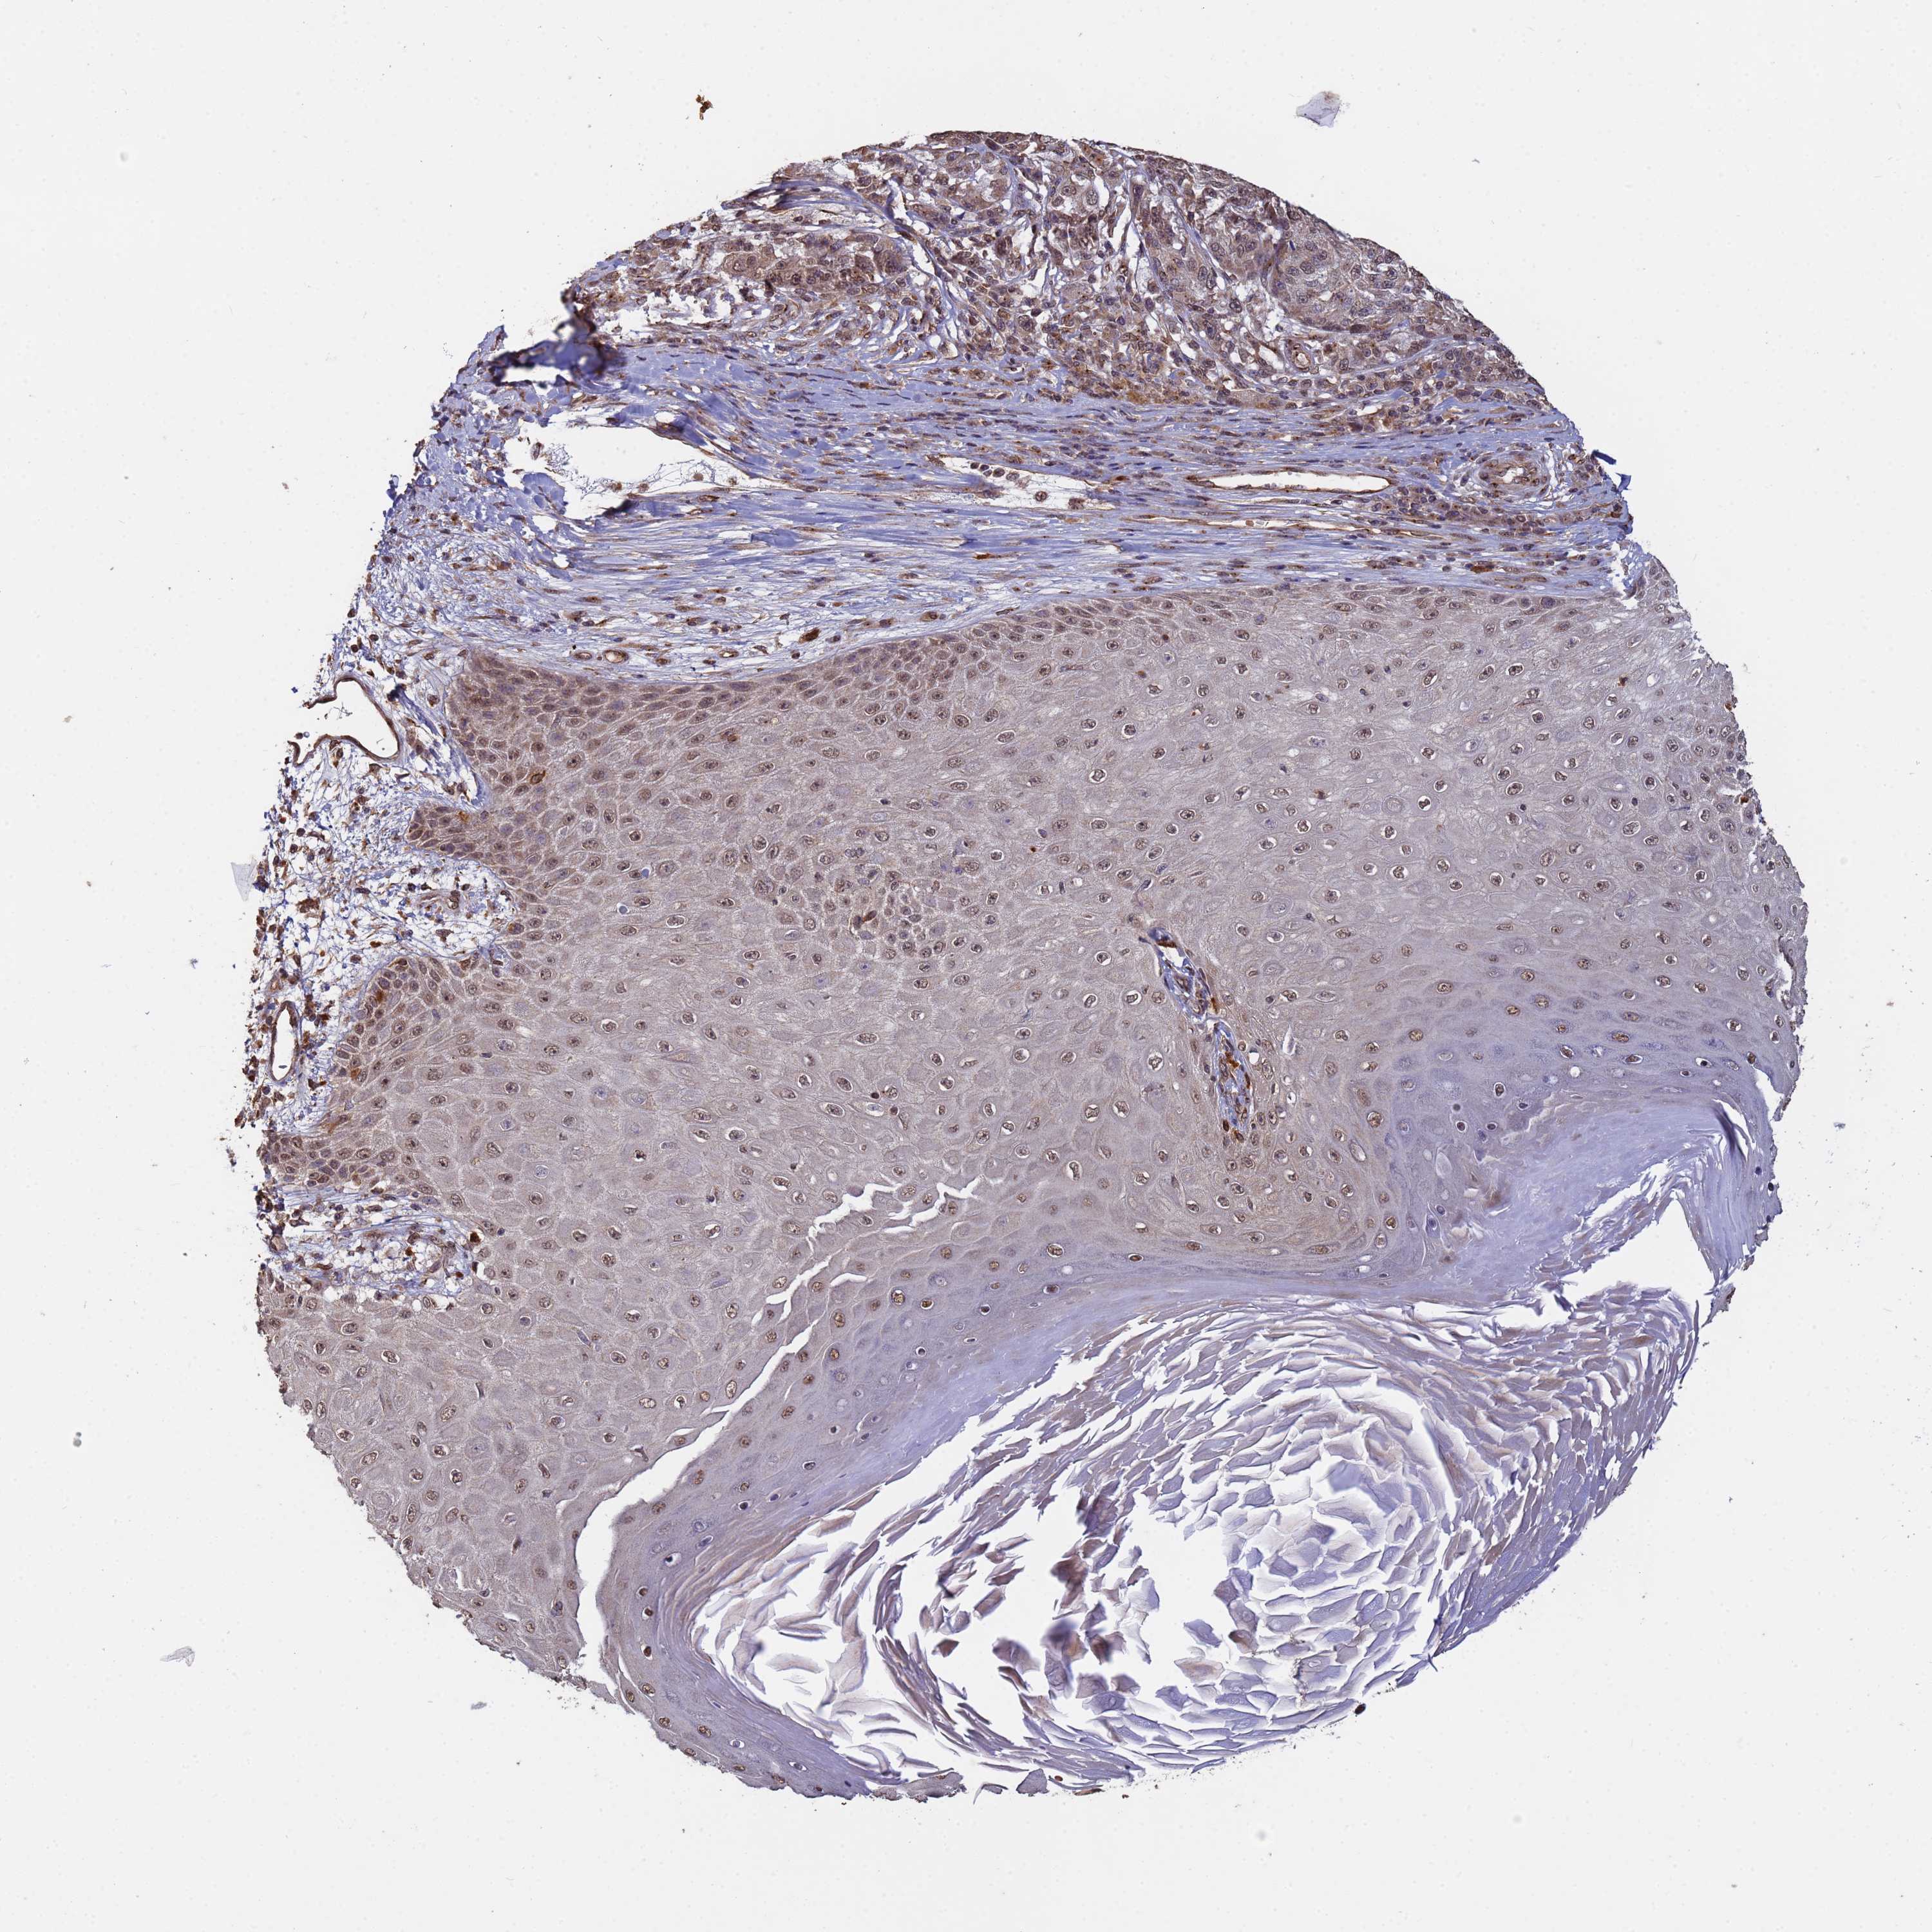

MELANOMA - Protein expressioni

A mouse-over function shows sample information and annotation data. Click on an image to view it in a full screen mode. Samples can be filtered based on level of antibody staining by selecting one or several of the following categories: high, medium, low and not detected. The assay and annotation is described here.

Note that samples used for immunohistochemistry by the Human Protein Atlas do not correspond to samples in the TCGA dataset.

Antibody stainingi

Antibody staining in the annotated cell types in the current human tissue is reported as not detected, low, medium, or high, based on conventional immunohistochemistry profiling in selected tissues. This score is based on the combination of the staining intensity and fraction of stained cells.

Each image is clickable and will lead to virtual microscopy that enables deeper exploration of all samples and also displays staining intensity scores, fraction scores and subcellular localization as well as patient and tissue information for each sample.

Antibody HPA045624

Staining

High

Medium

Low

Not detected

Intensity

Strong

Moderate

Weak

Negative

Quantity

>75%

75%-25%

<25%

None

Location

Nuclear

Cytoplasmic/membranous

Cytoplasmic/membranous,nuclear

Malignant melanoma, NOS

Malignant melanoma, Metastatic site